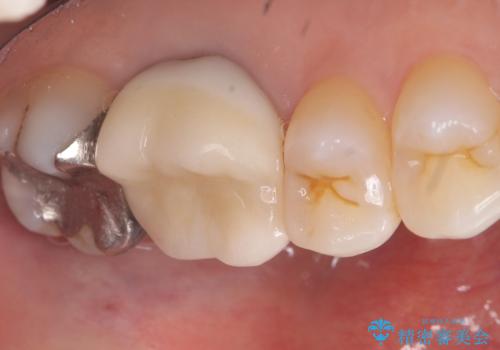

- 主訴:昔入れた銀の詰め物を白い物に替えて金属を無くしたい。

審美性、適合性の観点からセラミックインレーでのやり替えとなりました。

保険適用のメタルインレーを除去した際、下に広がっているカリエスも除去し形成印象を行いました。